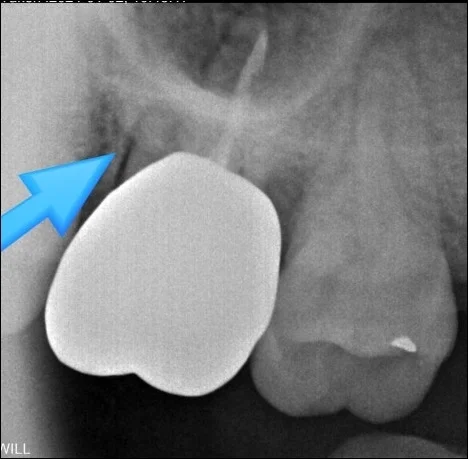

겉으로 보기에는 큰 문제가 없어 보일 수 있지만, 위 사진의 화살표 부분을 보면 알 수 있듯이 촬영 시 엑스레이 관구가 얼굴 주변을 회전하면서 귀걸이의 그림자가 치아 부위에 겹쳐 보일 수 있습니다.

이처럼 귀걸이의 허상이 영상에 나타나게 되면 정확한 판독에 방해가 될 수 있기 때문에, 파노라마 엑스레이 촬영 전에는 액세서리를 제거해 주시는 것이 필요합니다.